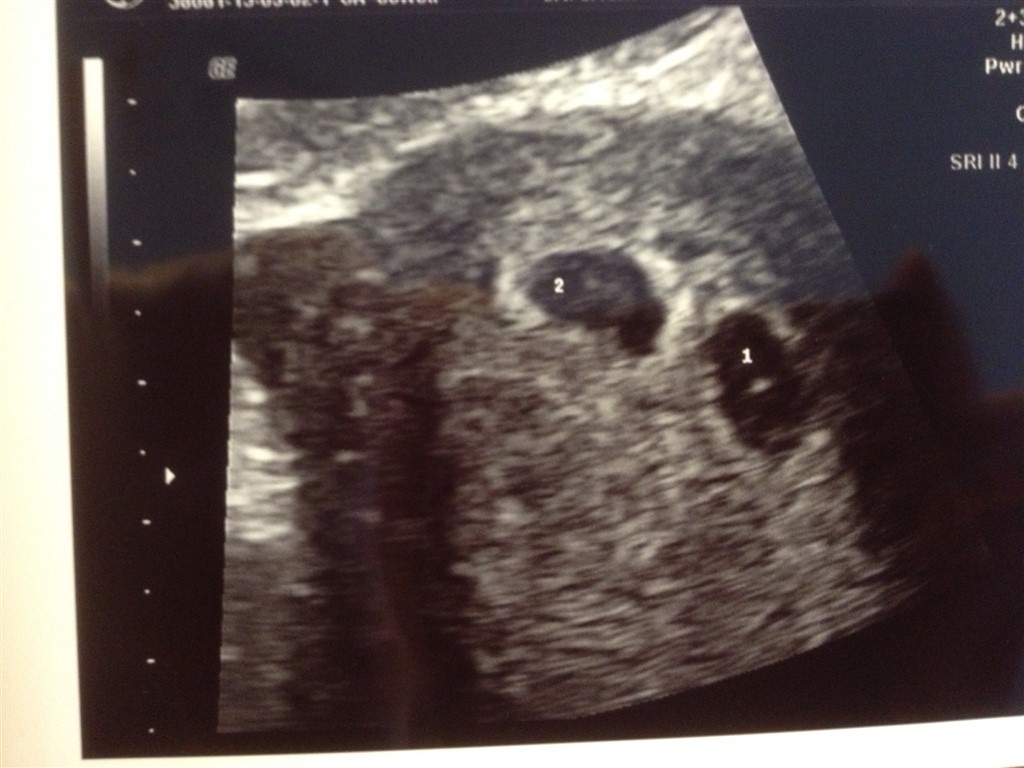

jeg skal til en termin scanning grundet lange cyklusser. Jeg vil gætte på, jeg er 4+ til 5+ til scanningen efter weekenden.

vil man kunne se, at man venter tveægget tvillinger omkring 4+ et eller andet?